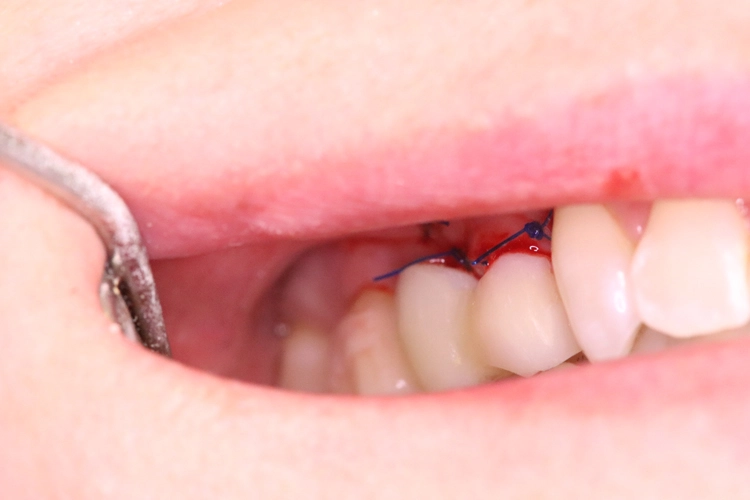

Der Erhalt der Weichgewebsstrukturen und des Kieferkamms wurde durch das Einbringen eines Knochenaufbaumaterials im Sinne einer Socket/Ridge Preservation ohne Membran gewährleistet (Abb. 5). Mesial zum 13 wurde eine resorbierbare Naht (SABAsorb rapid) gesetzt, um die Weichgewebe zu adaptieren. Die Kontrolle des Heilungsverlaufs nach dem Eingriff erfolgte ein Tag später (Abb. 6).

Während der Phase des Wundverschlusses ging ein geringer Bruchteil (1-2 %) des Knochenersatzmaterials verloren. Daher wird empfohlen, immer bis zum Gingivaniveau zu augmentieren. Dieser leichte Verlust spielt keine Rolle für den weiteren Knochenaufbau, der Patient merkt lediglich ein paar „Krümel“ im Mundraum.